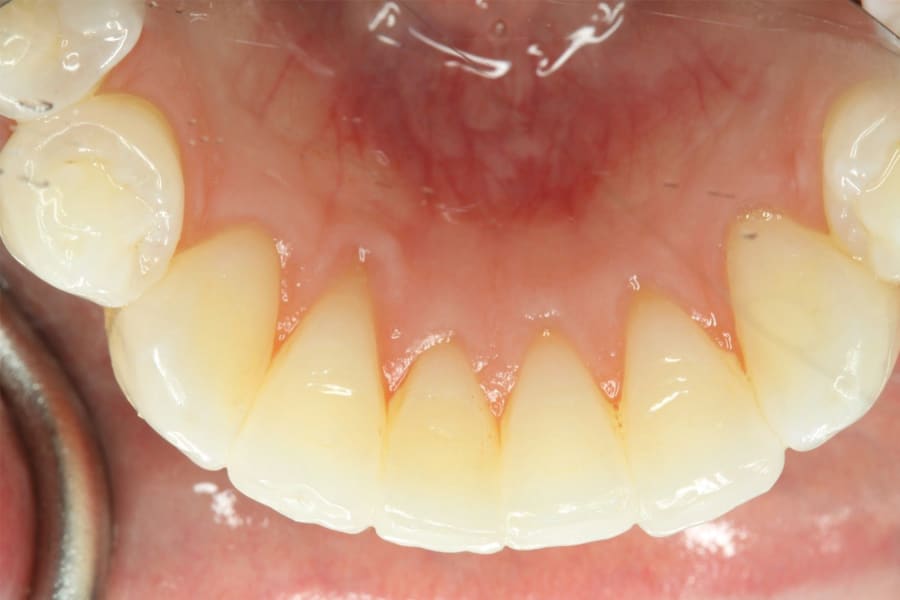

A second alternative is a laboratory-processed nickel-titanium splint (Figure 3) (Memotain®, AOA Lab, aoaaccess.com). The splint is manufactured via laser etching from a sheet of material conforming to a digital impression that is sent to a laboratory. Because the wire is not bent from stock, it is passive in nature and has no uncoiling tendency. It conforms accurately to tooth surfaces and is comfortable due to its streamlined design and intimate conformity. These characteristics also make it suitable as a splint when teeth are imperfectly aligned, as in a periodontally involved crowded dentition (Figure 4). Drawbacks of this design are the time and expense of laboratory fabrication.